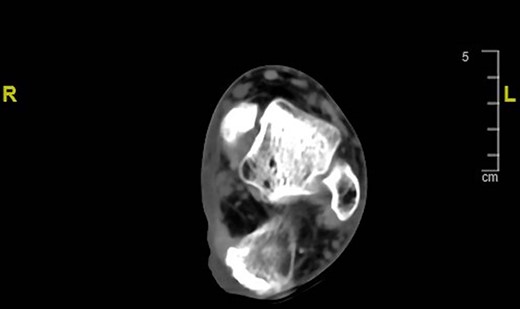

A 66-year-old man presented to our Clinic with recurrent ulceration on the left heel. The patient reported the amputation of the left forearm and a right below-knee amputation for a work accident about 30 years before, with a concomitant injury of the left heel and skin graft reconstruction. Since then, the patient has used a prosthetic leg for walking. Twenty years after the trauma, the patient underwent endovascular revascularization of the posterior tibial artery for peripheral arterial occlusive disease. He reported several ulcerations of the heel through the years which were treated conservatively. Wound examination revealed an ulcer (5.5 × 4.5 cm) with irregular edges and hypertrophic tissue, which was palpably indurated and fixed to the underlying subcutaneous tissues (Fig. 1). Multiple biopsies were performed and the histopathology report showed the presence of SCC. A staging whole-body computed tomography (CT) scan showed no distant metastases, and the lesion was strictly close to the calcaneus (Fig. 2). The patient underwent wide excision of the SCC with partial tangential calcanectomy. The heel defect was reconstructed with a medial plantar flap; the flap donor site was covered using Integra® Dermal Regeneration Template followed by skin grafting after 25 days (Fig. 3A–C). The histologic examination confirmed an ulcerated moderately differentiated SCC with free surgical margins. After tumor board multidisciplinary discussion, the patient started oncological follow-up.

Preoperative CT scan of the left foot showing the lesion strictly close to the calcaneus.